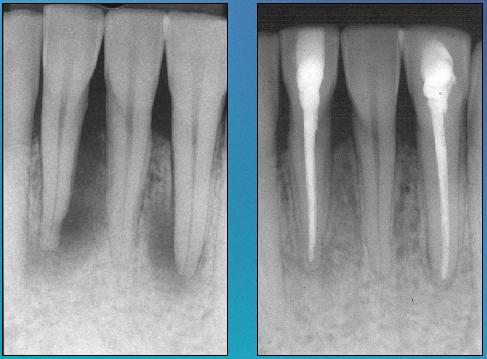

Men moet bedacht zijn op een endo/paro probleem als er een solitaire diepe bloedende pocket zit bij een vaak fors gevuld element. Zeker als er verder nauwelijks sprake is van parodontale problematiek. Patiënten geven soms aan dat ze bij “zuigen” een vieze smaak in de mond krijgen.

Uiteraard dient een X-foto te worden gemaakt. Soms is er een periapicale lucentie te zien.

Indien de oorsprong van de pocket van endodontische aard is dient er een endodontische behandeling te worden gedaan. De solitaire pocket (vergelijkbaar met een fistel) behoort vervolgens weer te verdwijnen.